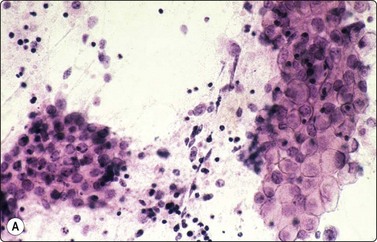

Tumors of more than one histologic type (mixed forms) (Figs 13.35 and 13.36)14,60,63,65

While the basic GCT types are infrequent in pure forms they are very frequent in mixed forms. Embryonal carcinoma and teratoma are each present in 47% of cases, and yolk sac tumors in 41%; 40% of TGCT contain varying numbers of syncytiotrophoblastic cells.12

image

Fig. 13.35 Tumor of more than one histological type (mixed form)

Large bisected tumor occupying most of the enlarged testicle in a male 19 years of age. Note hyalinized, degenerate and cystic areas.

image image

Fig. 13.36 Tumor of more than one histological type (mixed form)

(A) Well-differentiated glandular epithelium (right), large malignant cells similar to embryonal carcinoma (left) (MGG, HP); (B) Corresponding tissue section (A, H&E, IP; B, PAP, IP).

Criteria for diagnosis

Cellular aspirates; necrosis and hemorrhage frequent,

Three-dimensional clusters of epithelial malignant cells as described above

Coexisting teratomatous structures represented by mature or immature tissues originating from one or more blastodermal leaf: fusiform naked nuclei embedded in a myxoid background resembling embryonal mesenchyme; islets of cartilage; sheets of epithelial cells, which may be squamous, ciliated or intestinal (with goblet cells); bundles of fusiform cells with blunt ends reminiscent of leiomyoma; tight clusters of deeply stained bare nuclei may correspond to primitive neuroectodermal tissue.

The diagnosis of mixed forms is simple when malignant elements of an epithelial nature coexist with clear-cut teratomatous structures. Necrosis may obscure the neoplastic cells and the teratomatous component may be only minor or even absent. This can be explained by its greater cohesion causing under-representation in FNA samples. As a result, the differential diagnosis between mixed TGCT and embryonal carcinoma is sometimes difficult or impossible.14,59-61,65,66 The presence of multinucleated syncytial cells is not diagnostic of choriocarcinoma.